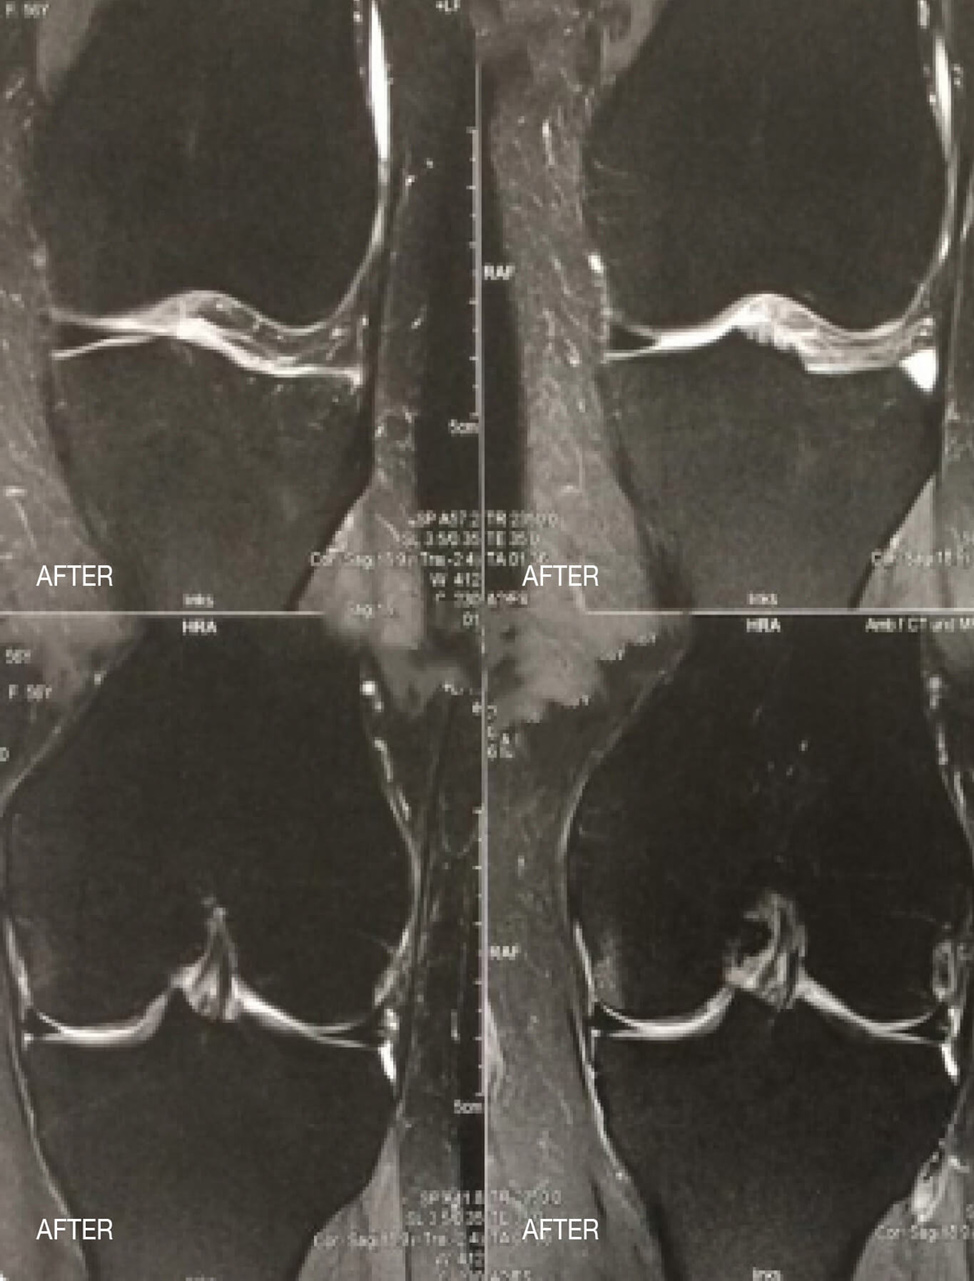

Las siguientes imágenes muestran un edema medular en la articulación de la rodilla antes y después de la terapia papimi. El tratamiento tuvo éxito tras sólo 10 sesiones.